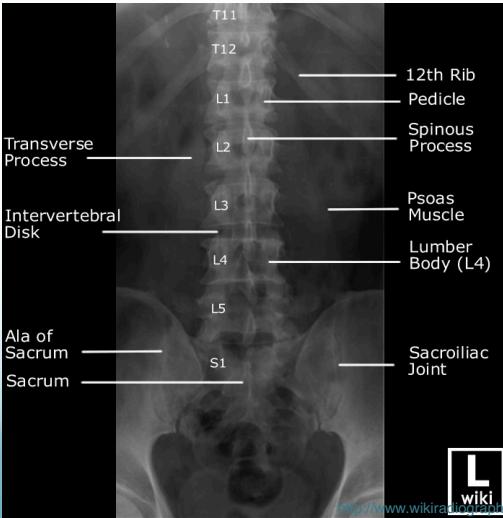

Radiographic (X-Ray) Views

- Standard Views: AP (Anteroposterior), LAT (Lateral)

Vertebral Segments

- 7 Cervical vertebrae

- 12 Thoracic vertebrae

- 5 Lumbar vertebrae

- 5 Sacral vertebrae (fused)

- 4 Coccygeal vertebrae (fused)